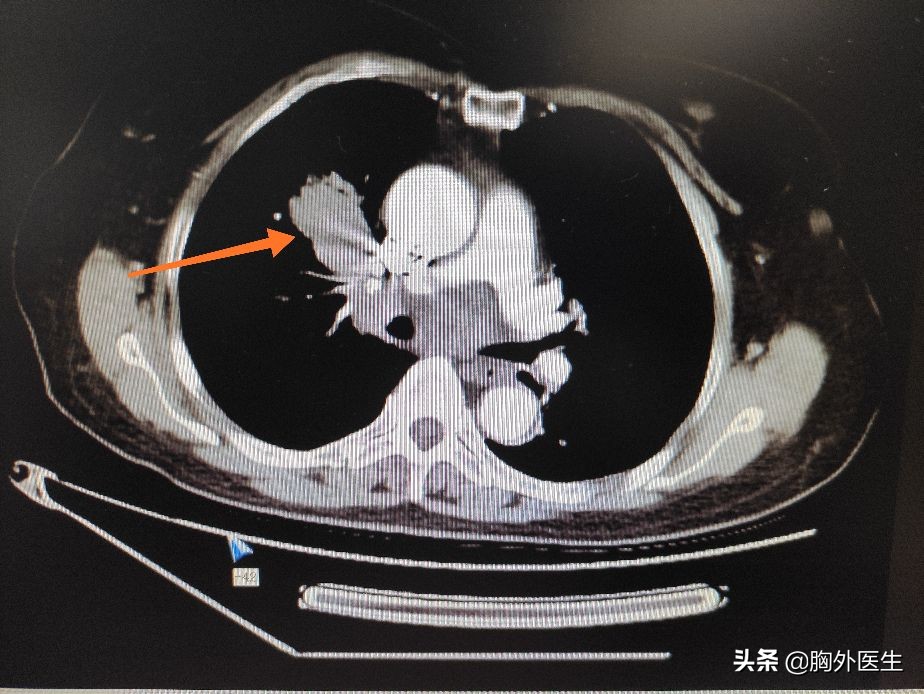

首先大家要明确一个概念,恶性肿瘤的治疗是一个综合的、个体化的治疗方案。在绝大多数实体肿瘤的治疗方案中,应当首先选择手术治疗,而且手术是目前唯一确定的有可能治愈肿瘤的方法。

但是,并不是每个人都适宜手术。有的人以为身体机能差不能耐受手术,有的人因为肿瘤分期太晚而不能手术。如果不能手术,还可以退而求其次选择放疗、化疗。放化疗对有些肿瘤也有一定的效果,可以改善生活质量、延长生存时间。